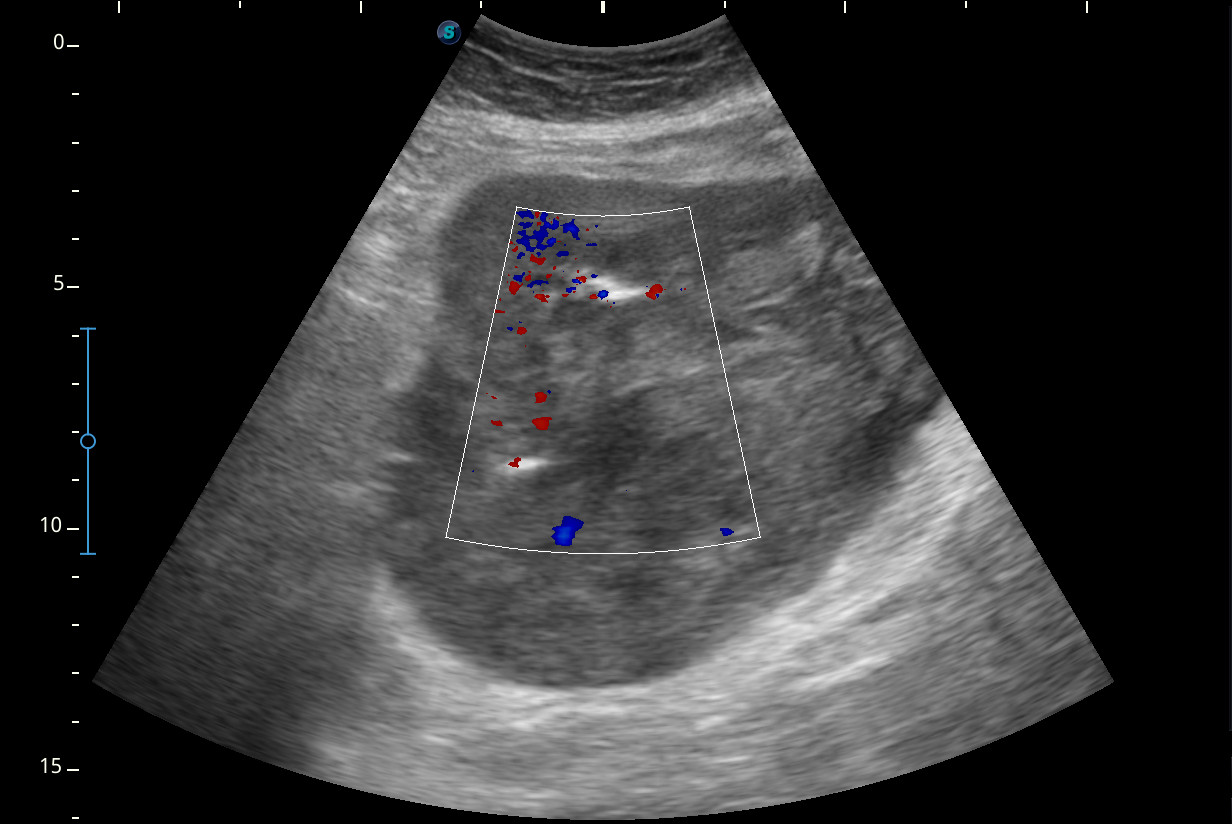

Se visualiza una masa heterogénea de unos 10 x 13 cm aproximadamente de diámetro con posibles focos necróticos y captación Doppler color, de dudosa organodependencia, que podría corresponder a un sarcoma retroperitoneal.